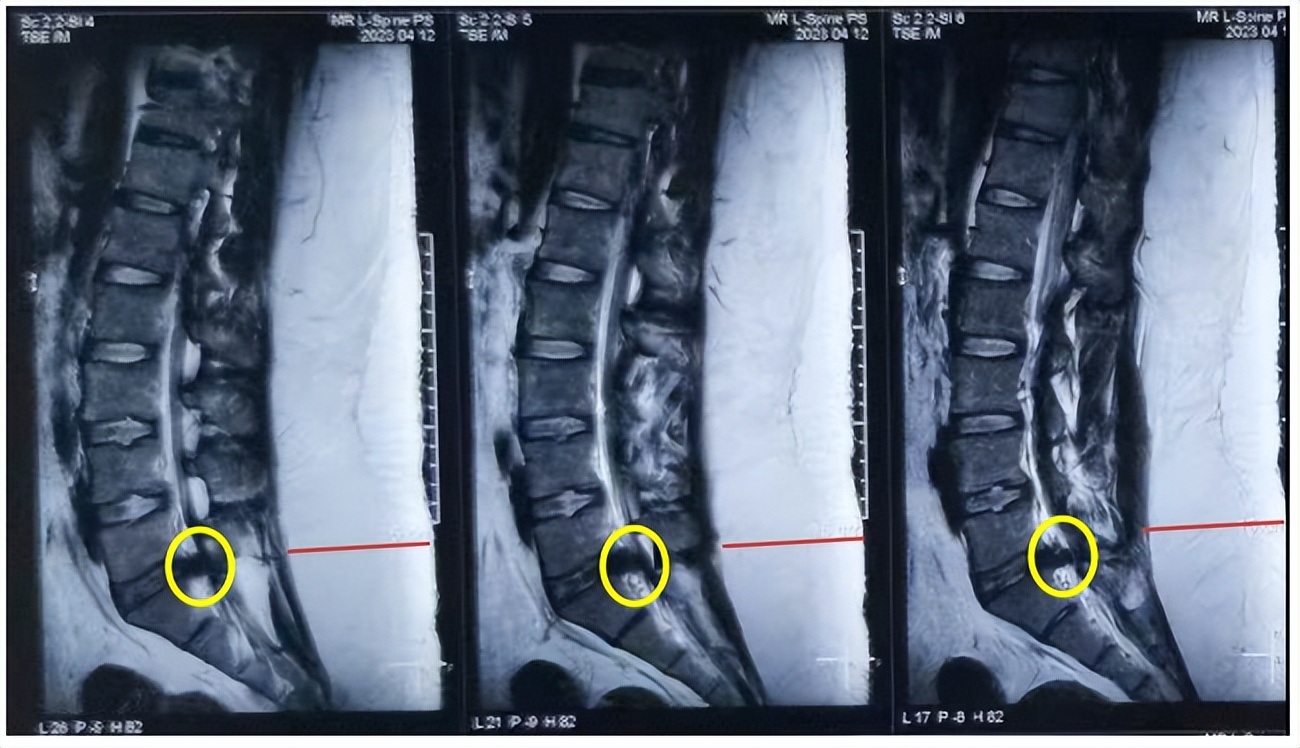

黄圈标记为脱出的间盘组织压迫神经